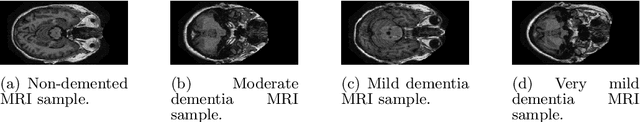

Abstract:Accurate and efficient classification of Alzheimer's disease (AD) severity from brain magnetic resonance imaging (MRI) remains a critical challenge, particularly when limited data and model interpretability are of concern. In this work, we propose TDA-Alz, a novel framework for four-stage Alzheimer's disease severity classification (non-demented, moderate dementia, mild, and very mild) using topological data analysis (TDA) and ensemble learning. Instead of relying on deep convolutional architectures or extensive data augmentation, our approach extracts topological descriptors that capture intrinsic structural patterns of brain MRI, followed by feature selection to retain the most discriminative topological features. These features are then classified using an ensemble learning strategy to achieve robust multiclass discrimination. Experiments conducted on the OASIS-1 MRI dataset demonstrate that the proposed method achieves an accuracy of 98.19% and an AUC of 99.75%, outperforming or matching state-of-the-art deep learning--based methods reported on OASIS and OASIS-derived datasets. Notably, the proposed framework does not require data augmentation, pretrained networks, or large-scale computational resources, making it computationally efficient and fast compared to deep neural network approaches. Furthermore, the use of topological descriptors provides greater interpretability, as the extracted features are directly linked to the underlying structural characteristics of brain MRI rather than opaque latent representations. These results indicate that TDA-Alz offers a powerful, lightweight, and interpretable alternative to deep learning models for MRI-based Alzheimer's disease severity classification, with strong potential for real-world clinical decision-support systems.

Abstract:Magnetic Resonance Imaging (MRI) plays a pivotal role in the early diagnosis and monitoring of Alzheimer's disease (AD). However, the subtle structural variations in brain MRI scans often pose challenges for conventional deep learning models to extract discriminative features effectively. In this work, we propose PseudoColorViT-Alz, a colormap-enhanced Vision Transformer framework designed to leverage pseudo-color representations of MRI images for improved Alzheimer's disease classification. By combining colormap transformations with the global feature learning capabilities of Vision Transformers, our method amplifies anatomical texture and contrast cues that are otherwise subdued in standard grayscale MRI scans. We evaluate PseudoColorViT-Alz on the OASIS-1 dataset using a four-class classification setup (non-demented, moderate dementia, mild dementia, and very mild dementia). Our model achieves a state-of-the-art accuracy of 99.79% with an AUC of 100%, surpassing the performance of recent 2024--2025 methods, including CNN-based and Siamese-network approaches, which reported accuracies ranging from 96.1% to 99.68%. These results demonstrate that pseudo-color augmentation combined with Vision Transformers can significantly enhance MRI-based Alzheimer's disease classification. PseudoColorViT-Alz offers a robust and interpretable framework that outperforms current methods, providing a promising tool to support clinical decision-making and early detection of Alzheimer's disease.